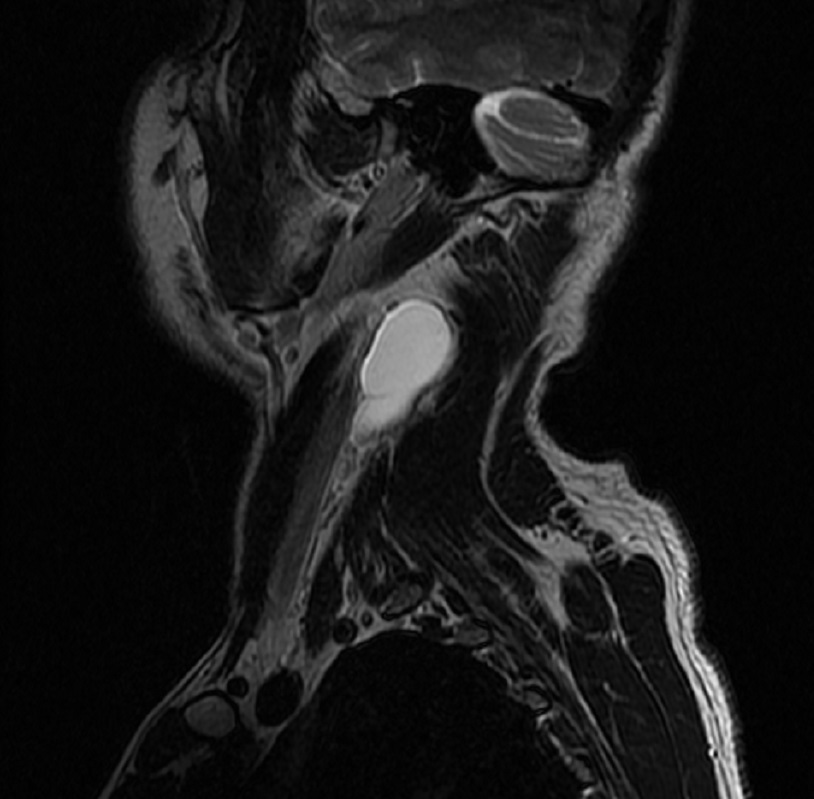

Thyroglossal duct cysts. Neck MRI – Detailed imaging of the cyst. Courtesy Dr. V. Penopoulos.